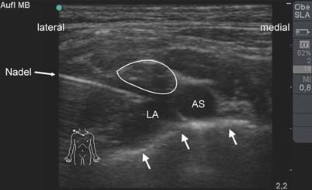

Abb. 2